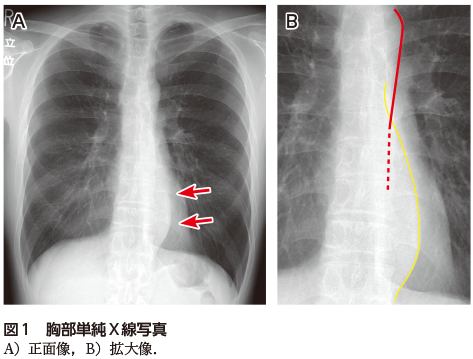

神経節腫は交感神経節を由来とする腫瘍で,小児〜若年成人に好発する.他の交感神経由来の腫瘍(神経節芽腫や神経芽腫)と比較して最も分化度の高い良性腫瘍である.画像所見は境界明瞭な円形や紡錘状・分葉状の腫瘤で,比較的内部均一な性状を示す.造影CTでは造影効果の弱いものや緩徐に造影される場合が多い(図2).後縦隔に多い神経鞘腫や神経線維腫などの神経原性腫瘍と比較すると,上下に長い紡錘形の形態を示すのが特徴的である.内部は粘液腫状変性をきたしやすく,CTでは低吸収,MRI T1強調像で筋肉よりも低信号,T2強調像は腫瘍内部の粘液基質や細胞成分,膠原線維などの割合を反映して中間信号〜高信号を示す.

図2